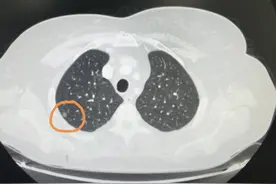

对于刚发现的直径比较小的肺磨玻璃结节,观察一段时间,看看它的变化,再决定是不是手术,是绝对安全的。有一位家住天津55岁的女士,偶然的原因拍胸部CT,发现了肺部有两个磨玻璃结节,她带着片子过来找我看,我看到这两个结节都比较靠近外周,大的那个有6毫米,看起来恶性的可能性比较大,但直径比较小,可以再观察一下。

简单来说,他们也和小孩子一样,从小婴儿开始慢慢成长,努力锻炼生存技巧,并最终获得侵袭转移的能力。而1cm以下的小肺癌尚处于襁褓期,侵袭性通常很弱,不会发生淋巴结转移,如果能在这个阶段进行干预,效果自然也很好。